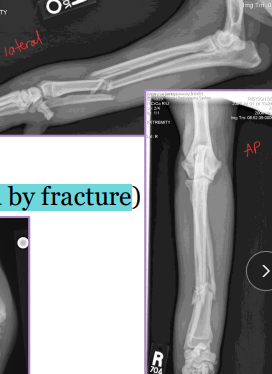

Tibia & fibula Fractures

Considerations: Common, Min soft tissue envelope, risk of open fracture

fibula broke concurrently, not broke in young

Tx:

Rx: Casting/splinting

closed, transverse fractures, >50% reduction, lateral splint (greenstick fractures)

Sx: Plate + screws, IM pin + cerclage, Interlocking nail, ESF